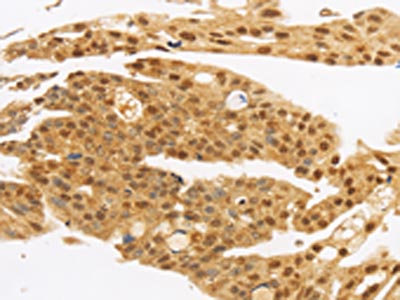

The image on the left is immunohistochemistry of paraffin-embedded Human liver cancer tissue using CSB-PA407491(c-Myc Tag Antibody) at dilution 1/10, on the right is treated with synthetic peptide. (Original magnification: ×200)

The image on the left is immunohistochemistry of paraffin-embedded Human gastic cancer tissue using CSB-PA407491(c-Myc Tag Antibody) at dilution 1/10, on the right is treated with synthetic peptide. (Original magnification: ×200)